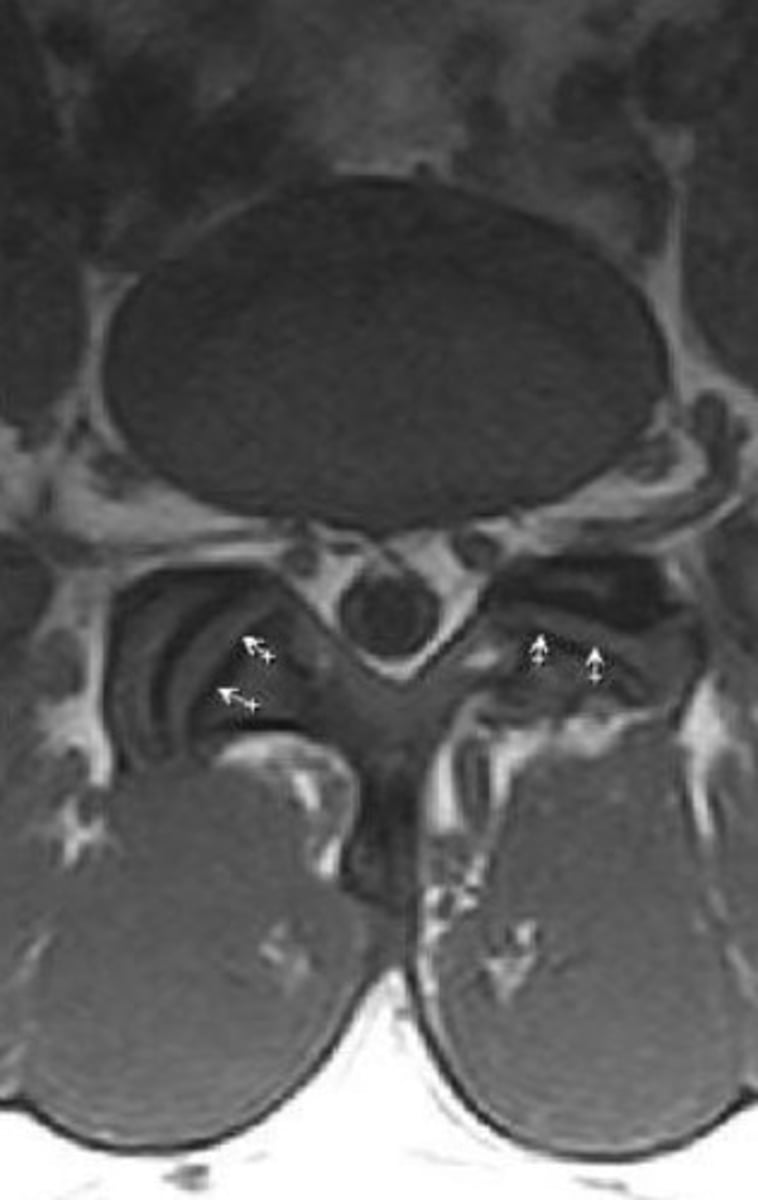

Facet Tropism

Asymmetric orientation of the facets = coronal AND sagittal facets at one level

What is the most sensitive study to see facet tropism? What is the necessary difference in angulation of the facet joints to be considered facet tropism?

CT studies

8 degrees or more difference = facet tropism